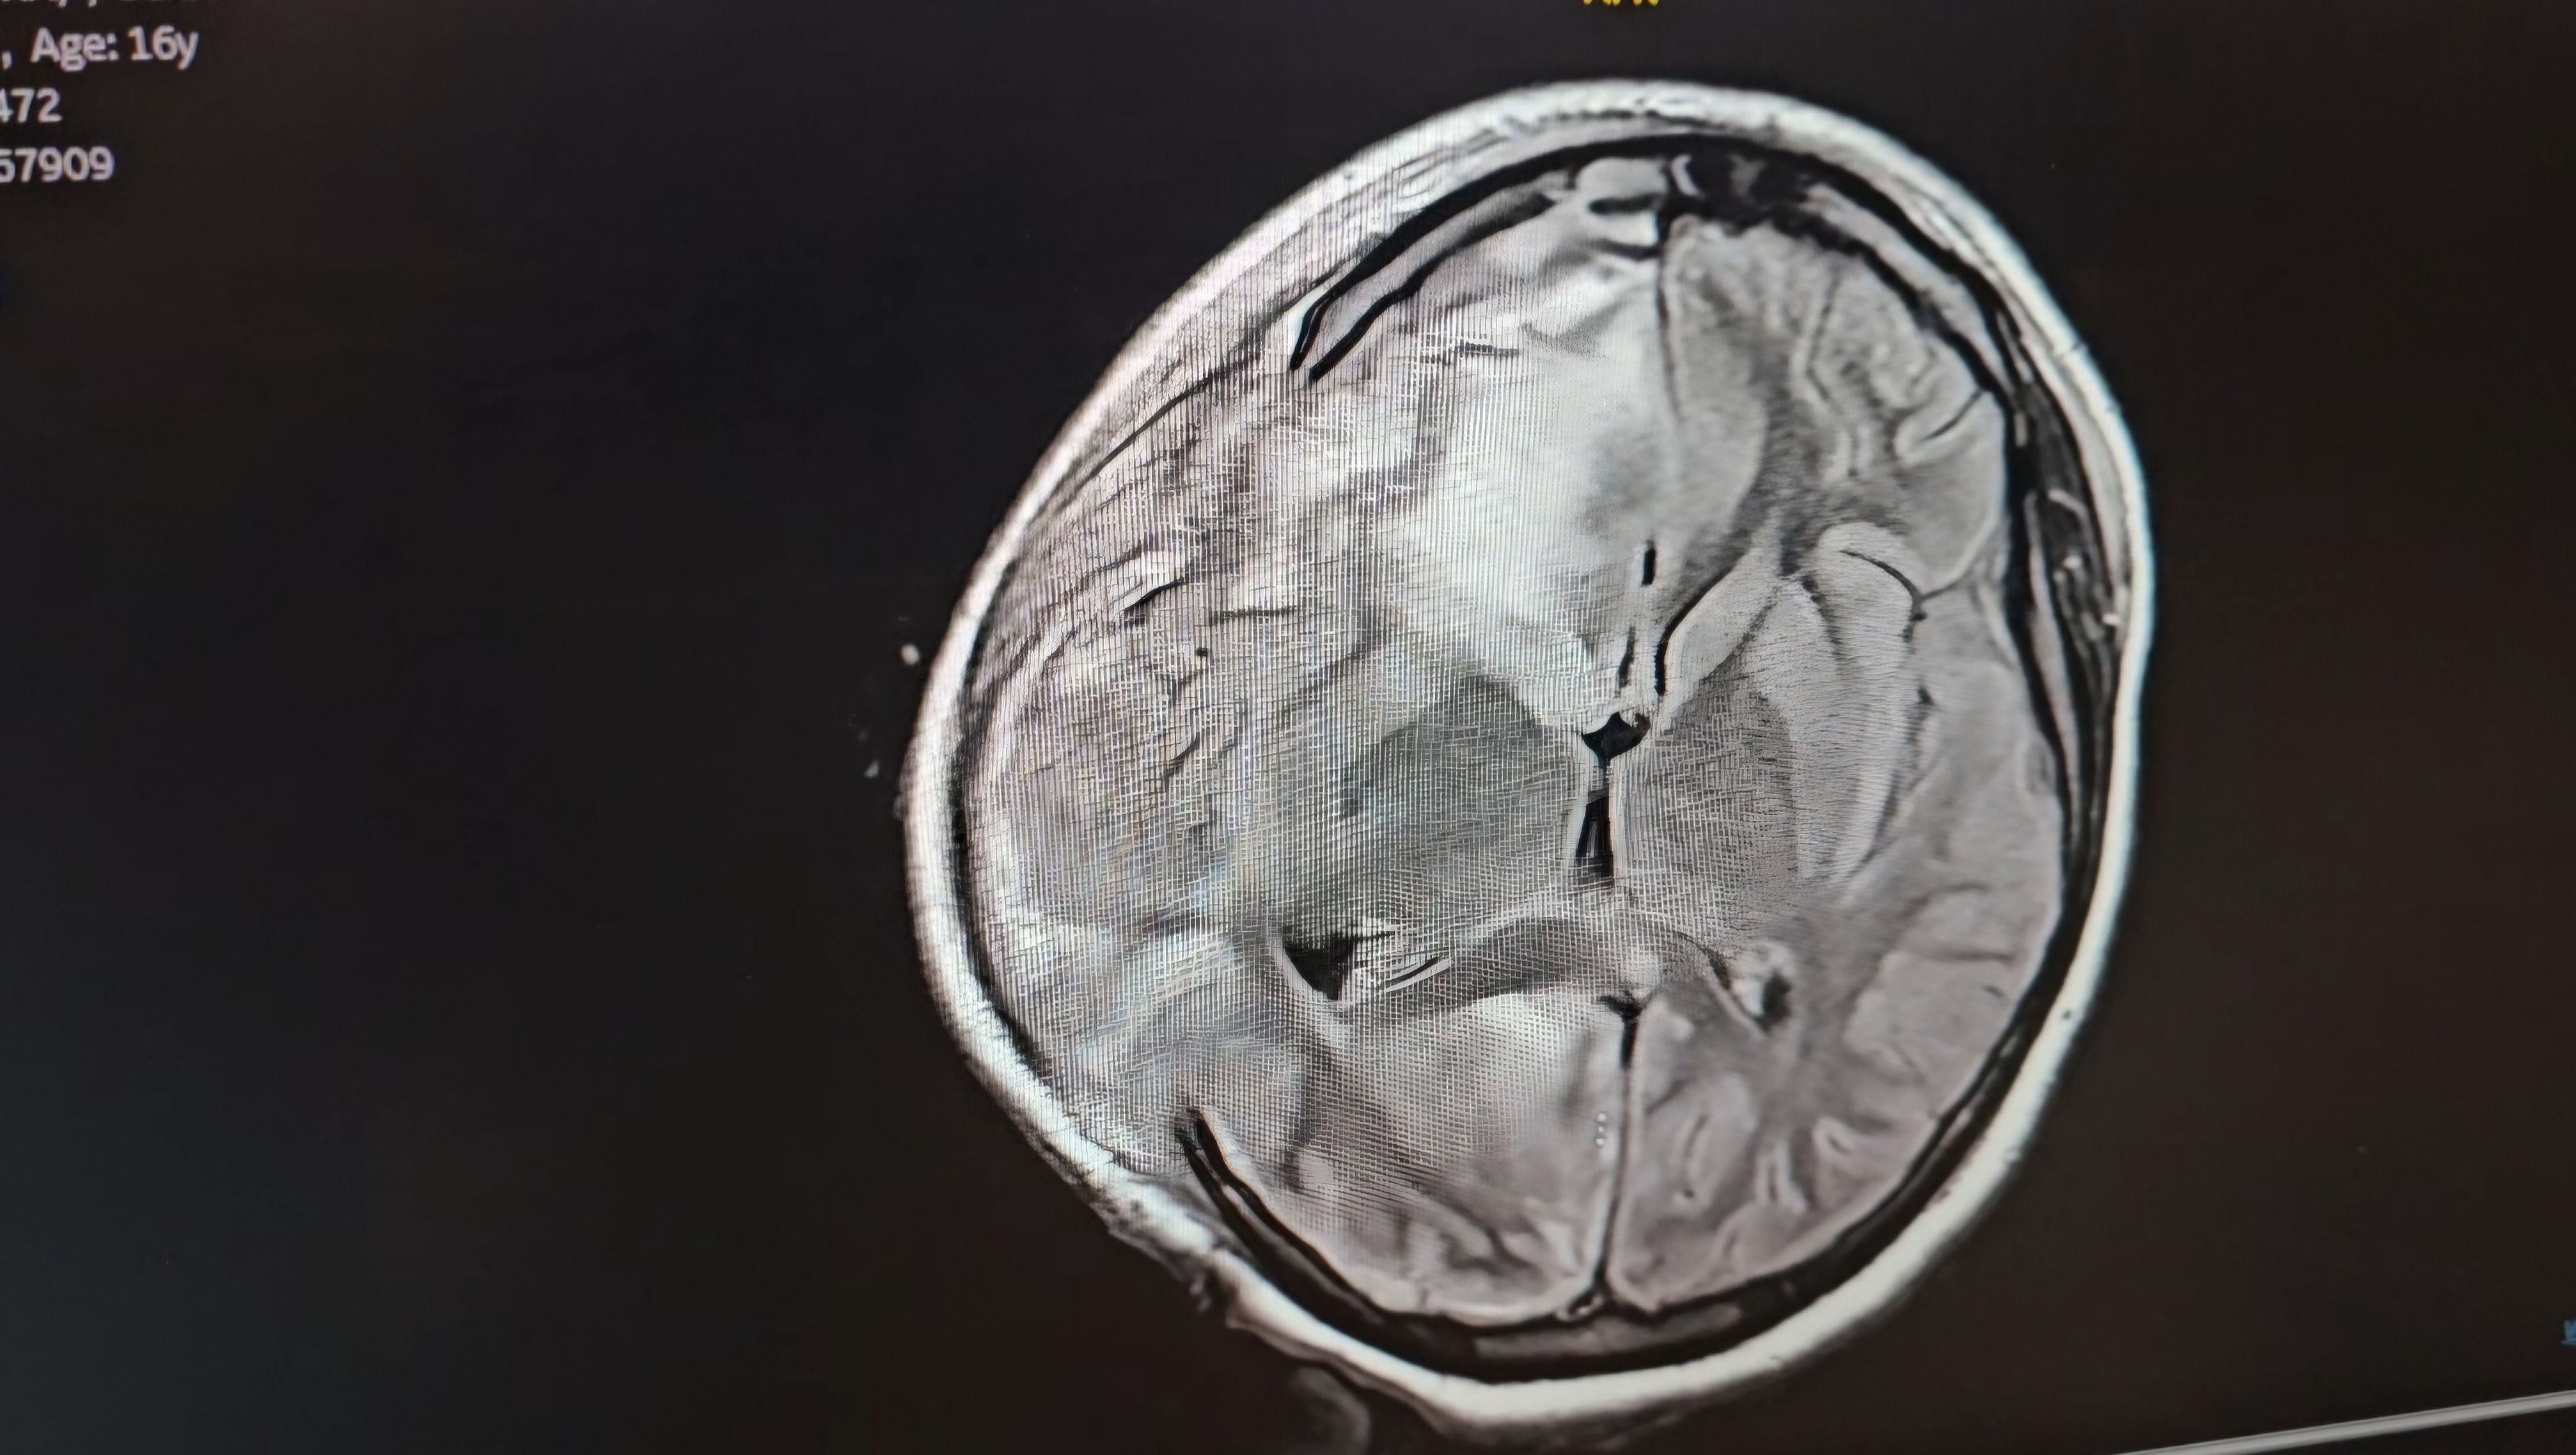

It all began with what seemed like a routine sinus infection, but quickly escalated to a life-threatening condition. The infection spread to the right side of her brain, causing serious complications. Alejandra is now nonverbal and unable to move the left side of her body, requiring multiple surgeries and ongoing medical care.

Her condition has been a constant rollercoaster of ups and downs, with moments of hope followed by heartbreaking setbacks. The infection has been diagnosed as a brain abscess, linked to Streptococcus intermedius—a rare and dangerous bacteria that has left her in a fragile state. The medical team is doing everything they can, but Alejandra’s prognosis remains uncertain, and her recovery journey will be long and difficult.

Alejandra’s case is part of a worrying trend. The infection that led to her brain abscess started as a sinus issue, and doctors are noticing more children developing similar infections that spread to the brain. Just last year, Dr. Taryn Bragg, Alejandra's surgeon, worked with the CDC to investigate a rise in brain abscess cases in children. These abscesses often follow common illnesses like sinus infections or earaches, but in some cases, they rapidly escalate to more serious conditions that require multiple surgeries.